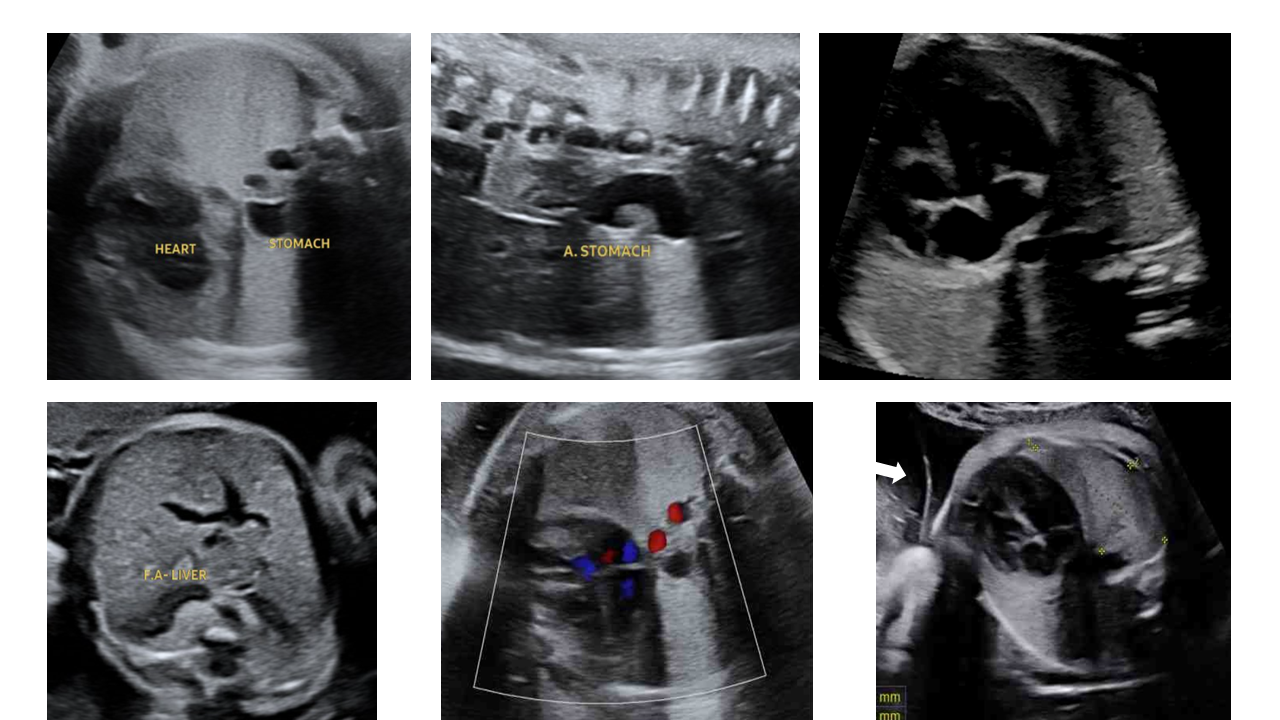

Thoát vị hoành - phải hay trái?